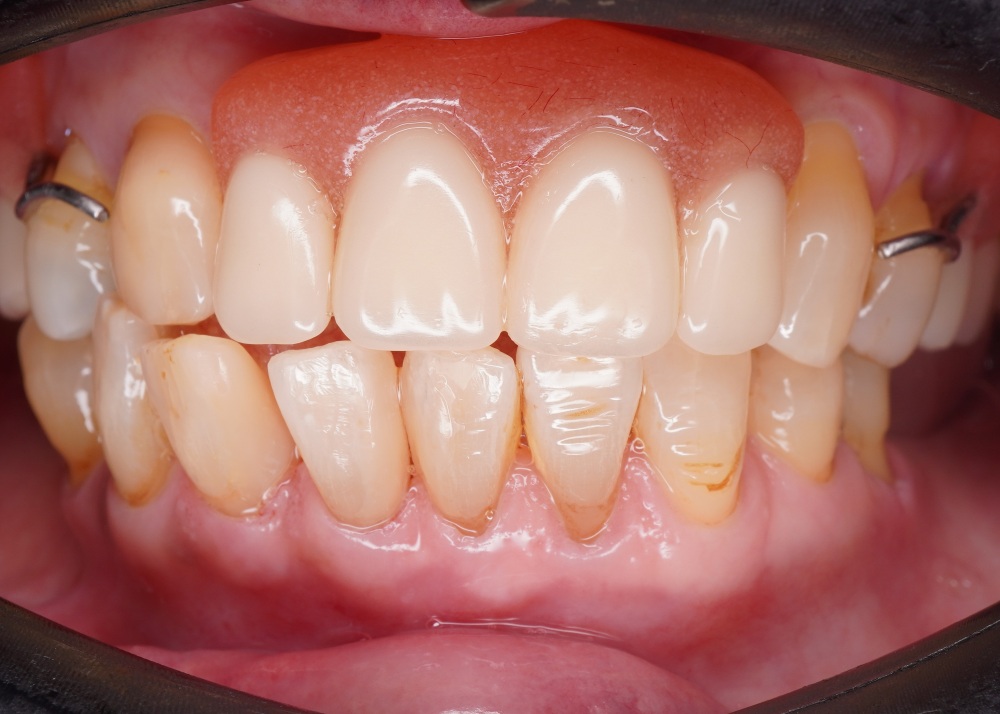

We use a digital intraoral scan to capture a detailed 3D image of your teeth and gums in real time. This helps us detect hidden issues such as cracks, gum problems, or early decay that may be causing your toothache.

For: Sensitive tooth and safeguard against decay

Bonus:

Stop micro-caries (initial stage of tooth decay) from growing by reducing bacteria and remineralizing the enamel

For: Sensitive tooth

Significant aesthetic improvement for anterior teeth